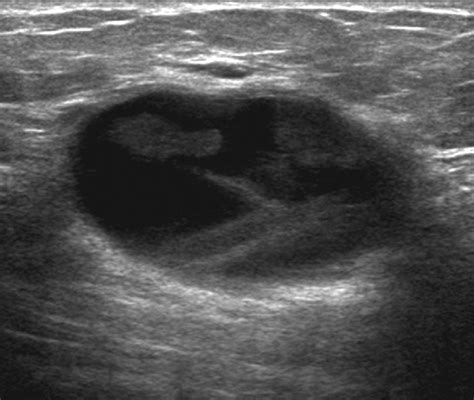

Interpreting the Results

After the Usg Of Breast is completed, a radiologist analyzes the images to look for specific characteristics. They evaluate the borders of a mass, its shape, and how it interacts with surrounding tissues. While an ultrasound is highly effective at identifying fluid-filled cysts—which are rarely cancerous—it is also used to flag solid masses that exhibit features concerning for malignancy. It is important to remember that not all masses identified on an ultrasound are cancerous. Many turn out to be benign fibroadenomas or normal glandular tissue.

In many cases, the radiologist will use the BI-RADS (Breast Imaging-Reporting and Data System) classification to standardize the report. This system helps doctors understand the level of suspicion and the recommended next steps, ranging from routine follow-ups to immediate diagnostic biopsies.